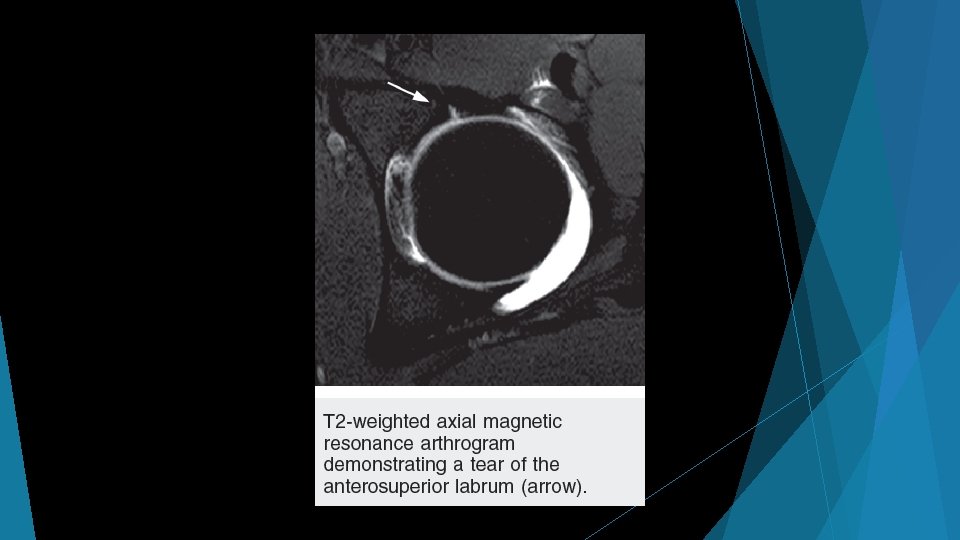

Shear forces on cartilage at chondrolabral junction Impingement with hip flexion Subtle findings on MRI: marcaine arthrogram with traction, 1. 5+ T MRI

Take-Home Points Student athlete with anterior groin pain, clicking/catching like knee meniscus Reduced hip ROM (especially decreased internal rotation) in young athlete Think Hip Labral Tear Think FAI If your doctor orders an MRI, encourage marcaine arthrogram study with traction Best sensitivity for labral tear, and diagnostic for intraarticular pain origin Refer to a hip arthroscopist if clinical concern for FAI/labral tear, verified intra-articular pathology, or failure to improve with several months of activity modification/therapy In patients >50 yo with recalcitrant “trochanteric bursitis, ” consider abductor tear and referral to hip arthroscopist